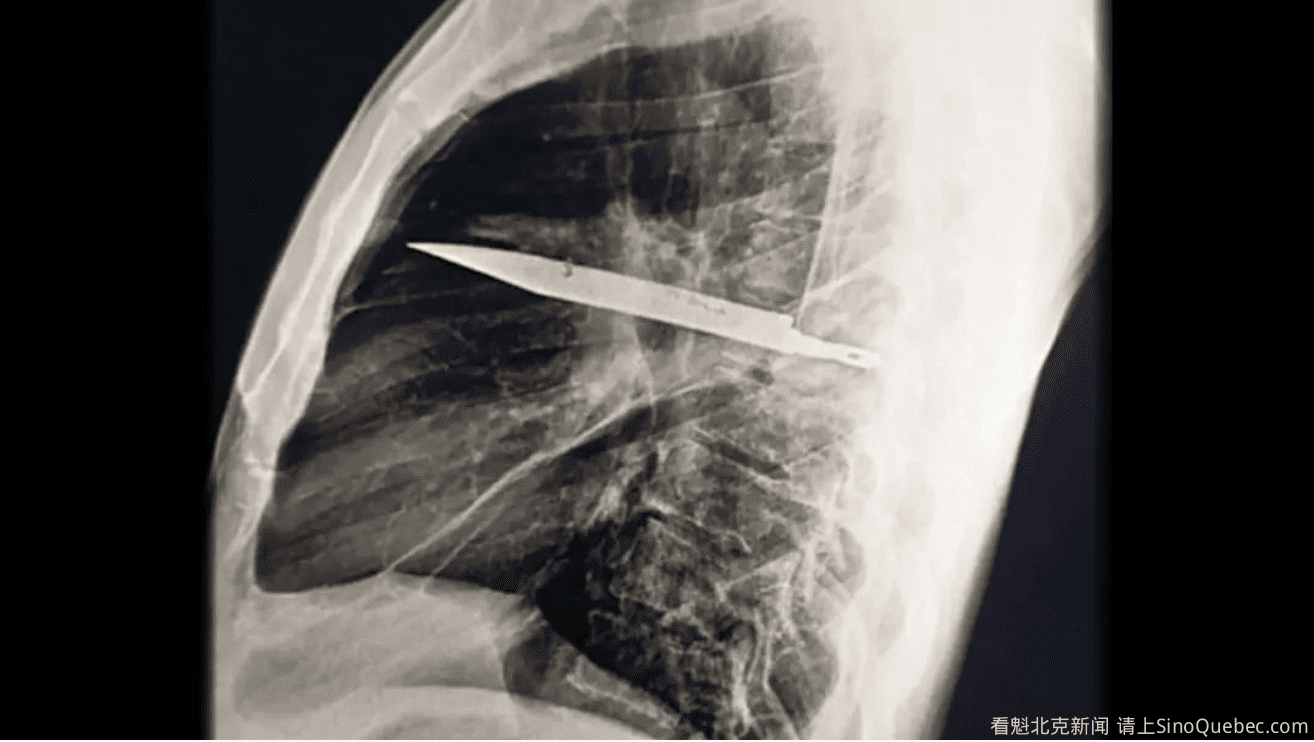

一天,一名 44 岁的坦桑尼亚男子出现在了当地医院的急诊室中。他说自己右乳头下方的胸部开口处连续 10 天有脓液渗出,但没有出现疼痛感或呼吸困难,也未出现发热,生命体征正常。 医生检查后发现,该男子右侧胸廓前部扁平,吸气时该侧胸部无法充分扩张。他们在病例报告中确认,乳头下方的腔洞有恶臭脓液渗出。 在检查过程中,该男子称,8 年前他在一场“暴力冲突”中胸部、背部、腹部和面部多次被刺伤。当时未进行任何影像学检查,仅对多处刀伤进行了表面急救处理。他表示,8 年来这些伤情并未引发任何健康问题。 X 光片显示,该男子胸腔内嵌有一把大型金属刀片。胸腔,亦称胸廓腔,位于腹部上方,是容纳心脏和肺部的空腔。这把断裂的刀从肋骨后侧延伸至前侧,自其右肩胛骨附近刺入背部。 刀片从患者背侧的第五和第六根肋骨之间滑入,随后卡在了那里,刀尖则位于胸腔前侧的第三和第四根肋骨之间。CT 扫描显示,其肩胛骨及多根肋骨存在已愈合的骨折。刀片周围被层层脓液及坏死或濒死组织所包裹。 人体通过一种称为纤维囊形成的过程来保护自己免受异物侵害,即免疫系统用胶原蛋白和其他纤维将物体包裹起来,以限制周围组织的损伤和炎症。据报道,这种对刀具的包裹很可能是让该男子在接下来的 8 年里都没有意识到胸部有刀片存在的原因。 外科医生随即实施了开胸手术,切开患者胸壁取出刀片。他们引流了积聚的脓液,用氯化钠溶液冲洗胸腔,安装引流管后缝合伤口。术后患者接受了为期七天的广谱抗生素治疗,并受到严密监护以防感染迹象。 术后第八天,医生拔除了引流管,两天后该男子出院。他随后返回医院进行了两次复查:一次在术后两周,另一次在术后六周。两次复查均显示无感染迹象,且未出现其他并发症。 该病例的独特之处在于:胸部遭受创伤性损伤后,穿刺物部分或全部遗留在胸腔内并不罕见。然而,多数情况下,这些异物是小型弹道抛射物,如子弹,它们往往难以定位和取出。 患者胸部 X 光片显示,一把大刀片卡在胸腔中部。图片来源:Kivuyo et al. J Surg Case Rep. 2025 May 31;2025(6):rjaf325; CC BY 4.0 这张 CT 扫描图(左)显示了男子胸腔内遗留的刀片,而三维重建的胸部 CT 图像(右)则同时展示了这把刀及其引发的相关骨骼损伤 图片来源:Kivuyo et al. J Surg Case Rep. 2025 May 31;2025(6):rjaf325; CC BY 4.0 相比之下,医学文献中较少记录到大型碎片——整个刀片或其他刺入性武器断裂并嵌入胸腔的情况。据报告显示,在大多数情况下,这些物体不会连续多年未被察觉,通常会在数周或数月内被发现并取出。 |